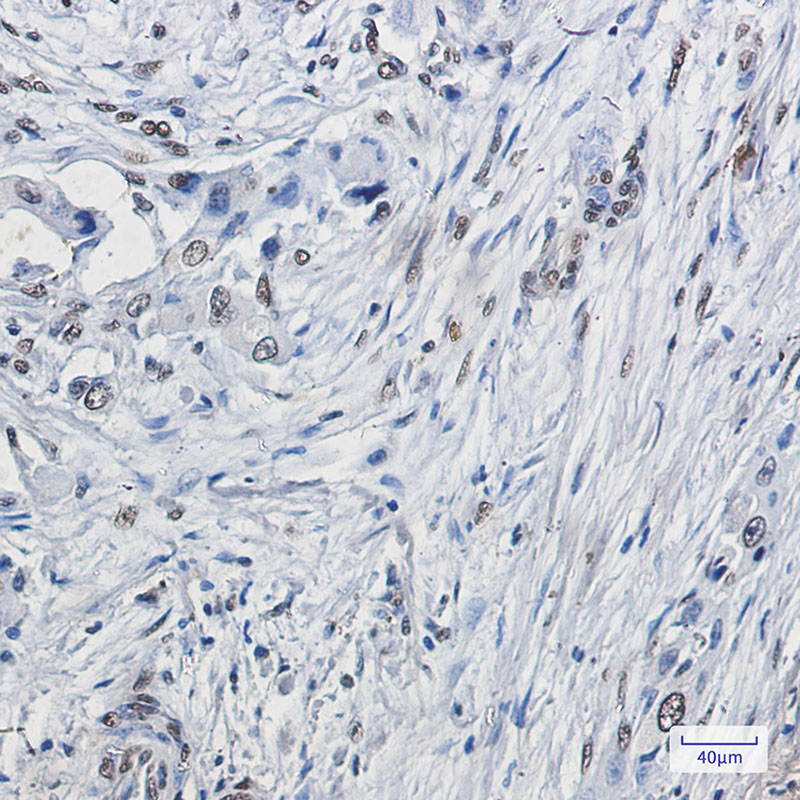

Product Image

| IHC | 1/50-1/100 |